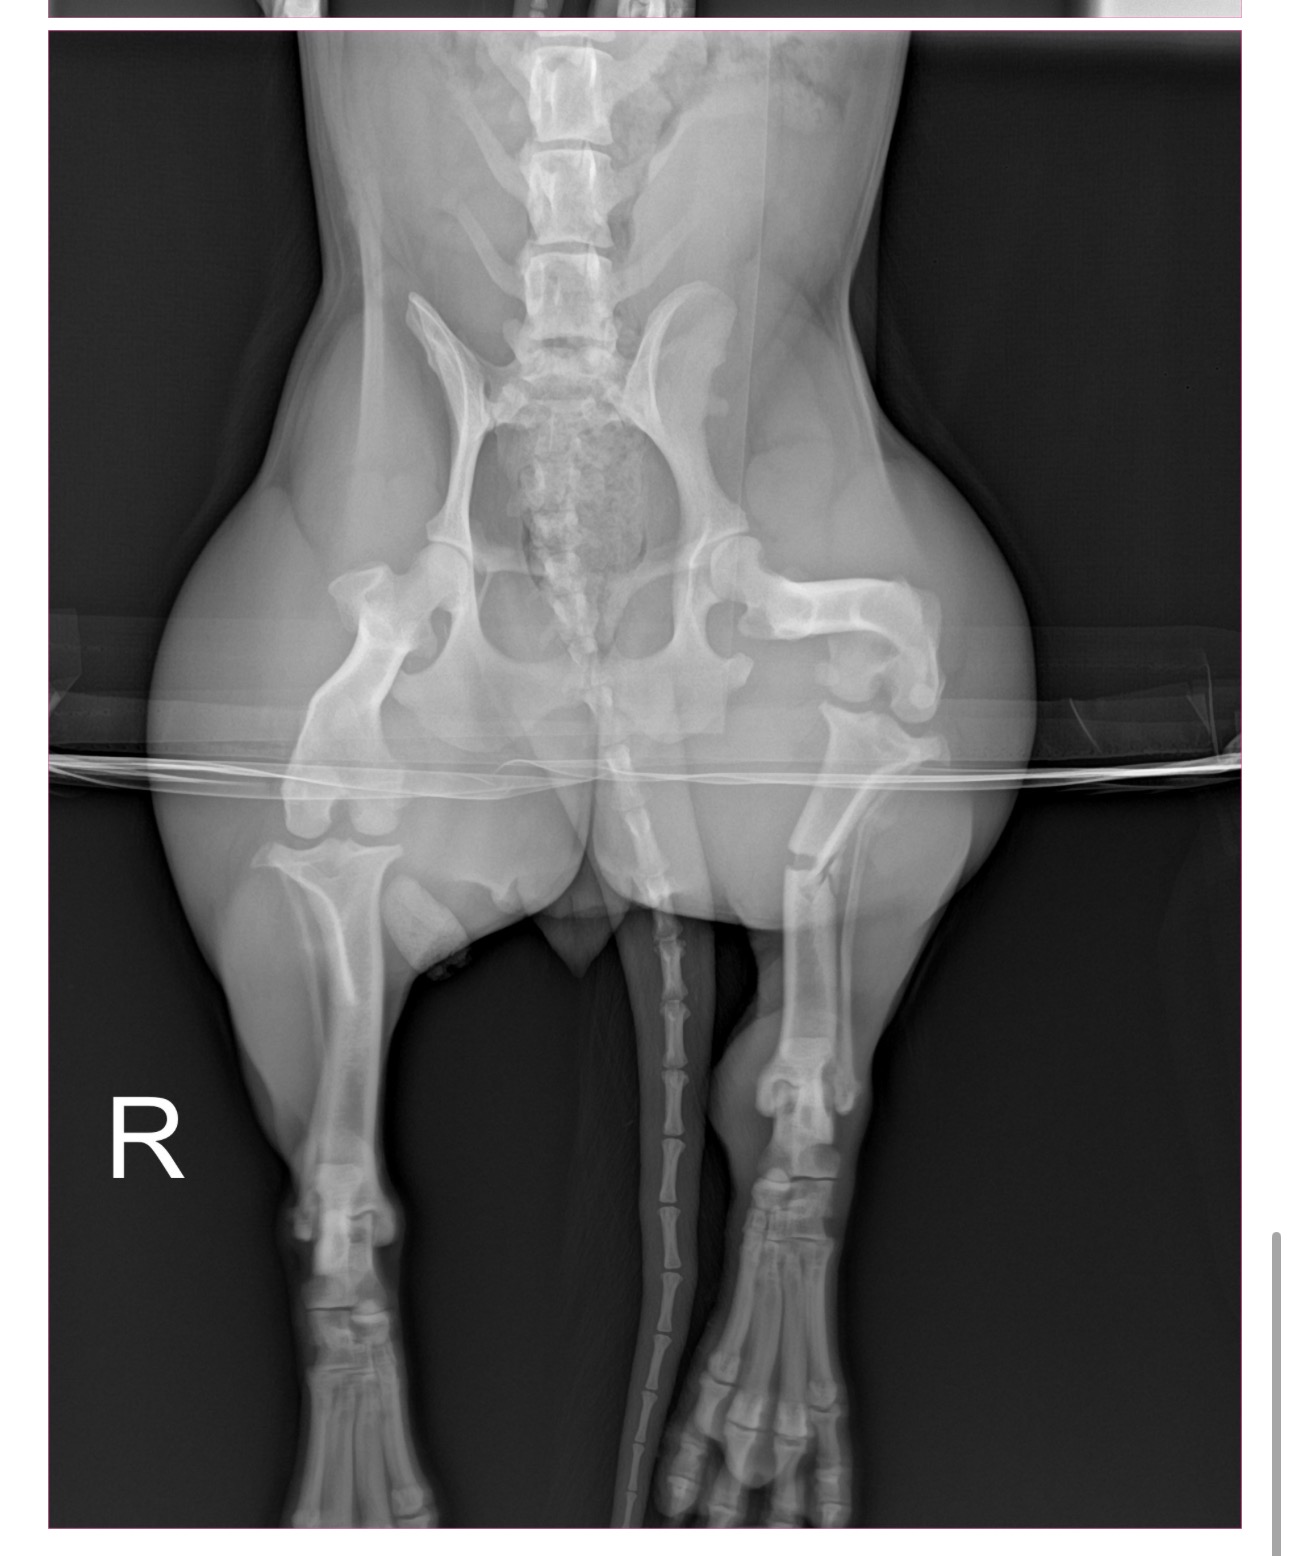

Hello, my name is Luna . I’m a playful, loving pup who enjoys spending time with my pup family and the neighborhood kids. Recently, while I was happily playing and with the excitement I ran out to the street and was struck by a car. Sadly, the driver didn’t stop to help — it was a hit and run.

The driver ran over my left foot, tore my skin burning off my fur, resulting with a broken femur. I was rushed to the vet hospital and given medication for the pain, I urgently need surgery to heal and be able to run and play again. Without surgery, my leg will not heal correctly, and I will continue to be in pain.